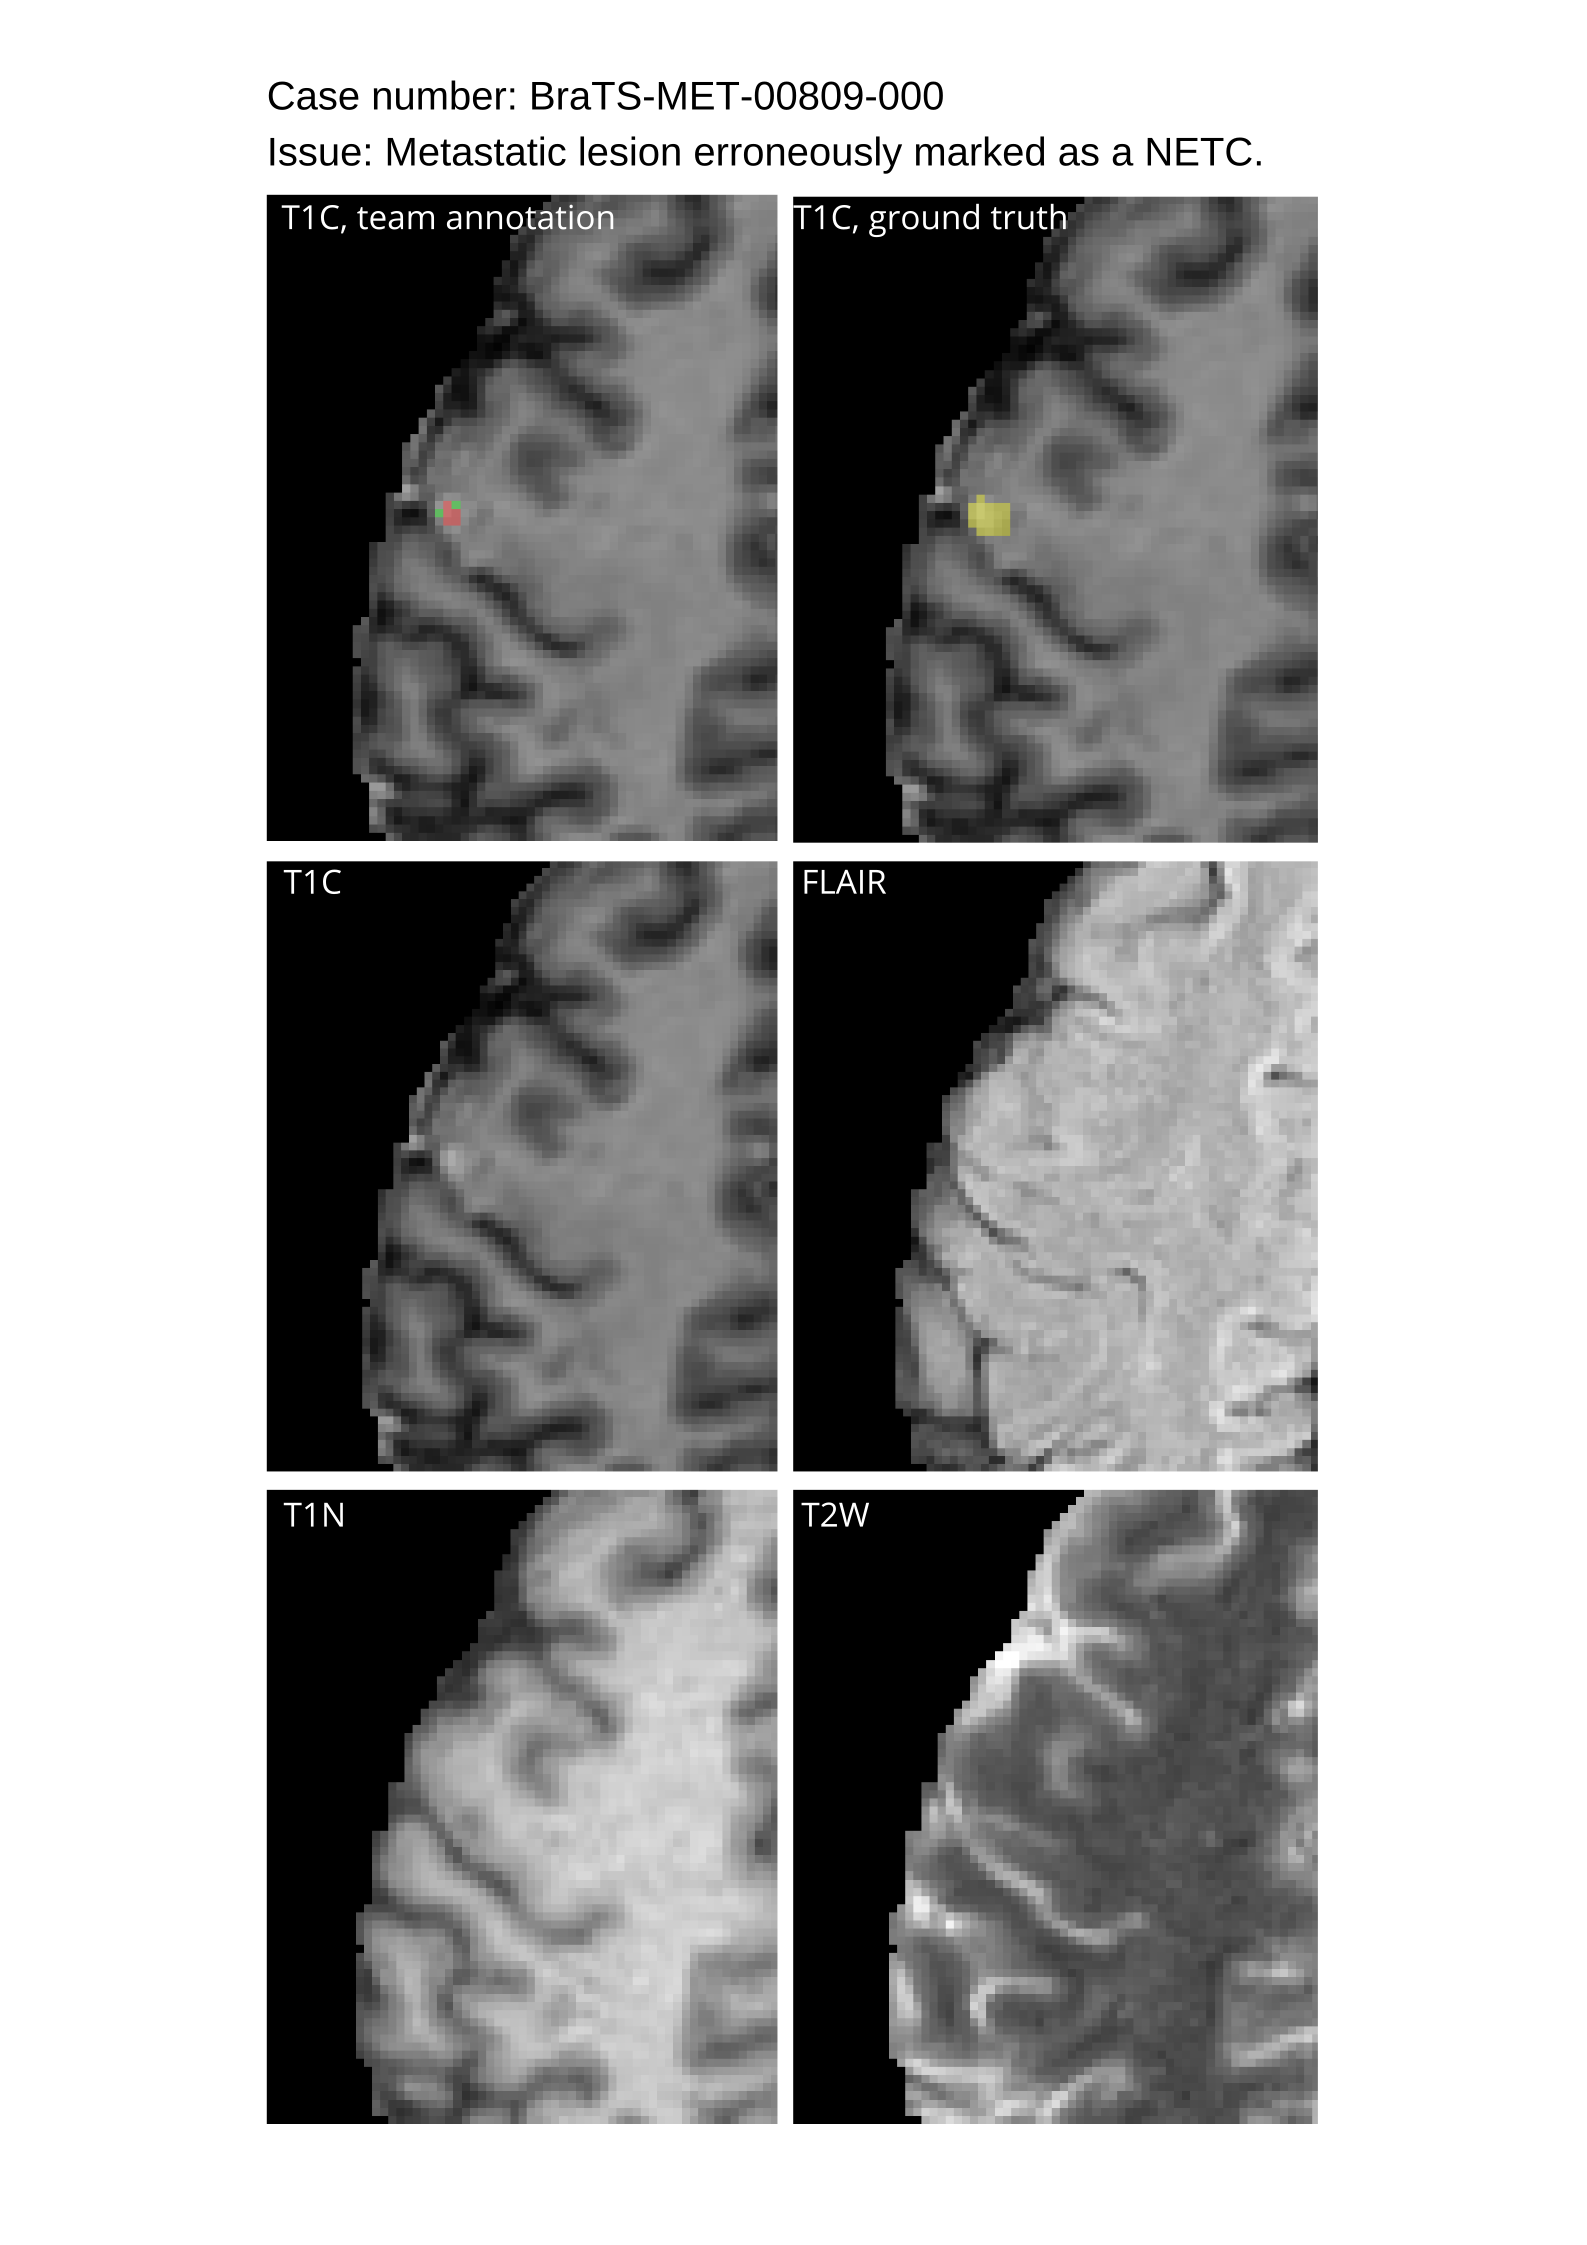

4.3 Tumor Labels

The annotation of tumor sub-regions aligned with Visually AcceSAble Rembrandt Images (VASARI) feature visibility and encompassed three labels: Gd-enhancing tumor (ET - label 3), surrounding non-enhancing FLAIR hyperintensity (SNFH - label 2), and the non-enhancing tumor core (NETC – label 1). ET is described as the enhancing portion of the tumor, characterized by areas of hyperintensity in T1Gd that are brighter than T1. NETC is identified as the presumed necrotic core of the tumor, which is evident as a non-enhancing focus surrounded by enhancing tumor. SNFH is defined as the peritumoral edema and tumor infiltrated tissue, indicated by the abnormal hyperintense signal on the T2-FLAIR images, which includes the infiltrative non-enhancing tumor, as well as vasogenic edema in the peritumoral region. In previous BraTS challenges, ET was segmented as label 4. However, starting from BraTS 2023, ET has been segmented as label 3 for consistency. The sub-regions are shown in Figure 2.

Approvers reviewed the volunteer annotations and either approved the case or returned it to students for re-annotation. Additionally, a QC process was implemented, which included removing all random voxels and any voxels outside the brain mask, ensuring all images had the same parameters (space, orientation, and origin) as the SRI24 atlas, and verifying the presence of all segmentations and segmentation masks are in the folder with original NIfTI images.